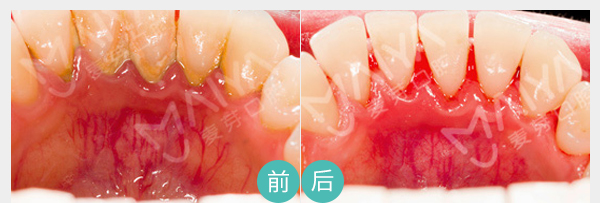

有助于医生判断病情、

并跟踪治疗效果

麦芽数字牙周治疗